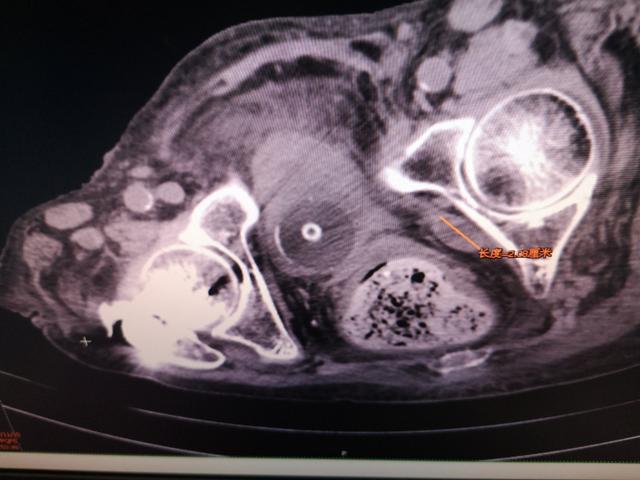

患者再次住院是2018年11月22日,以“嗜睡2天”急诊入院。急诊头部CT、心电图、心肌酶谱检查,除外了心脑血管意外相关疾病后,以“嗜睡待查 肝性脑病?”再次收入消化内科,急查血氨:88umol/L。入院后行全腹CT检查,发现:腹水明显减少,而且腹腔占位明显缩小。该患经两天对症治疗,很快清醒,1周后出院。